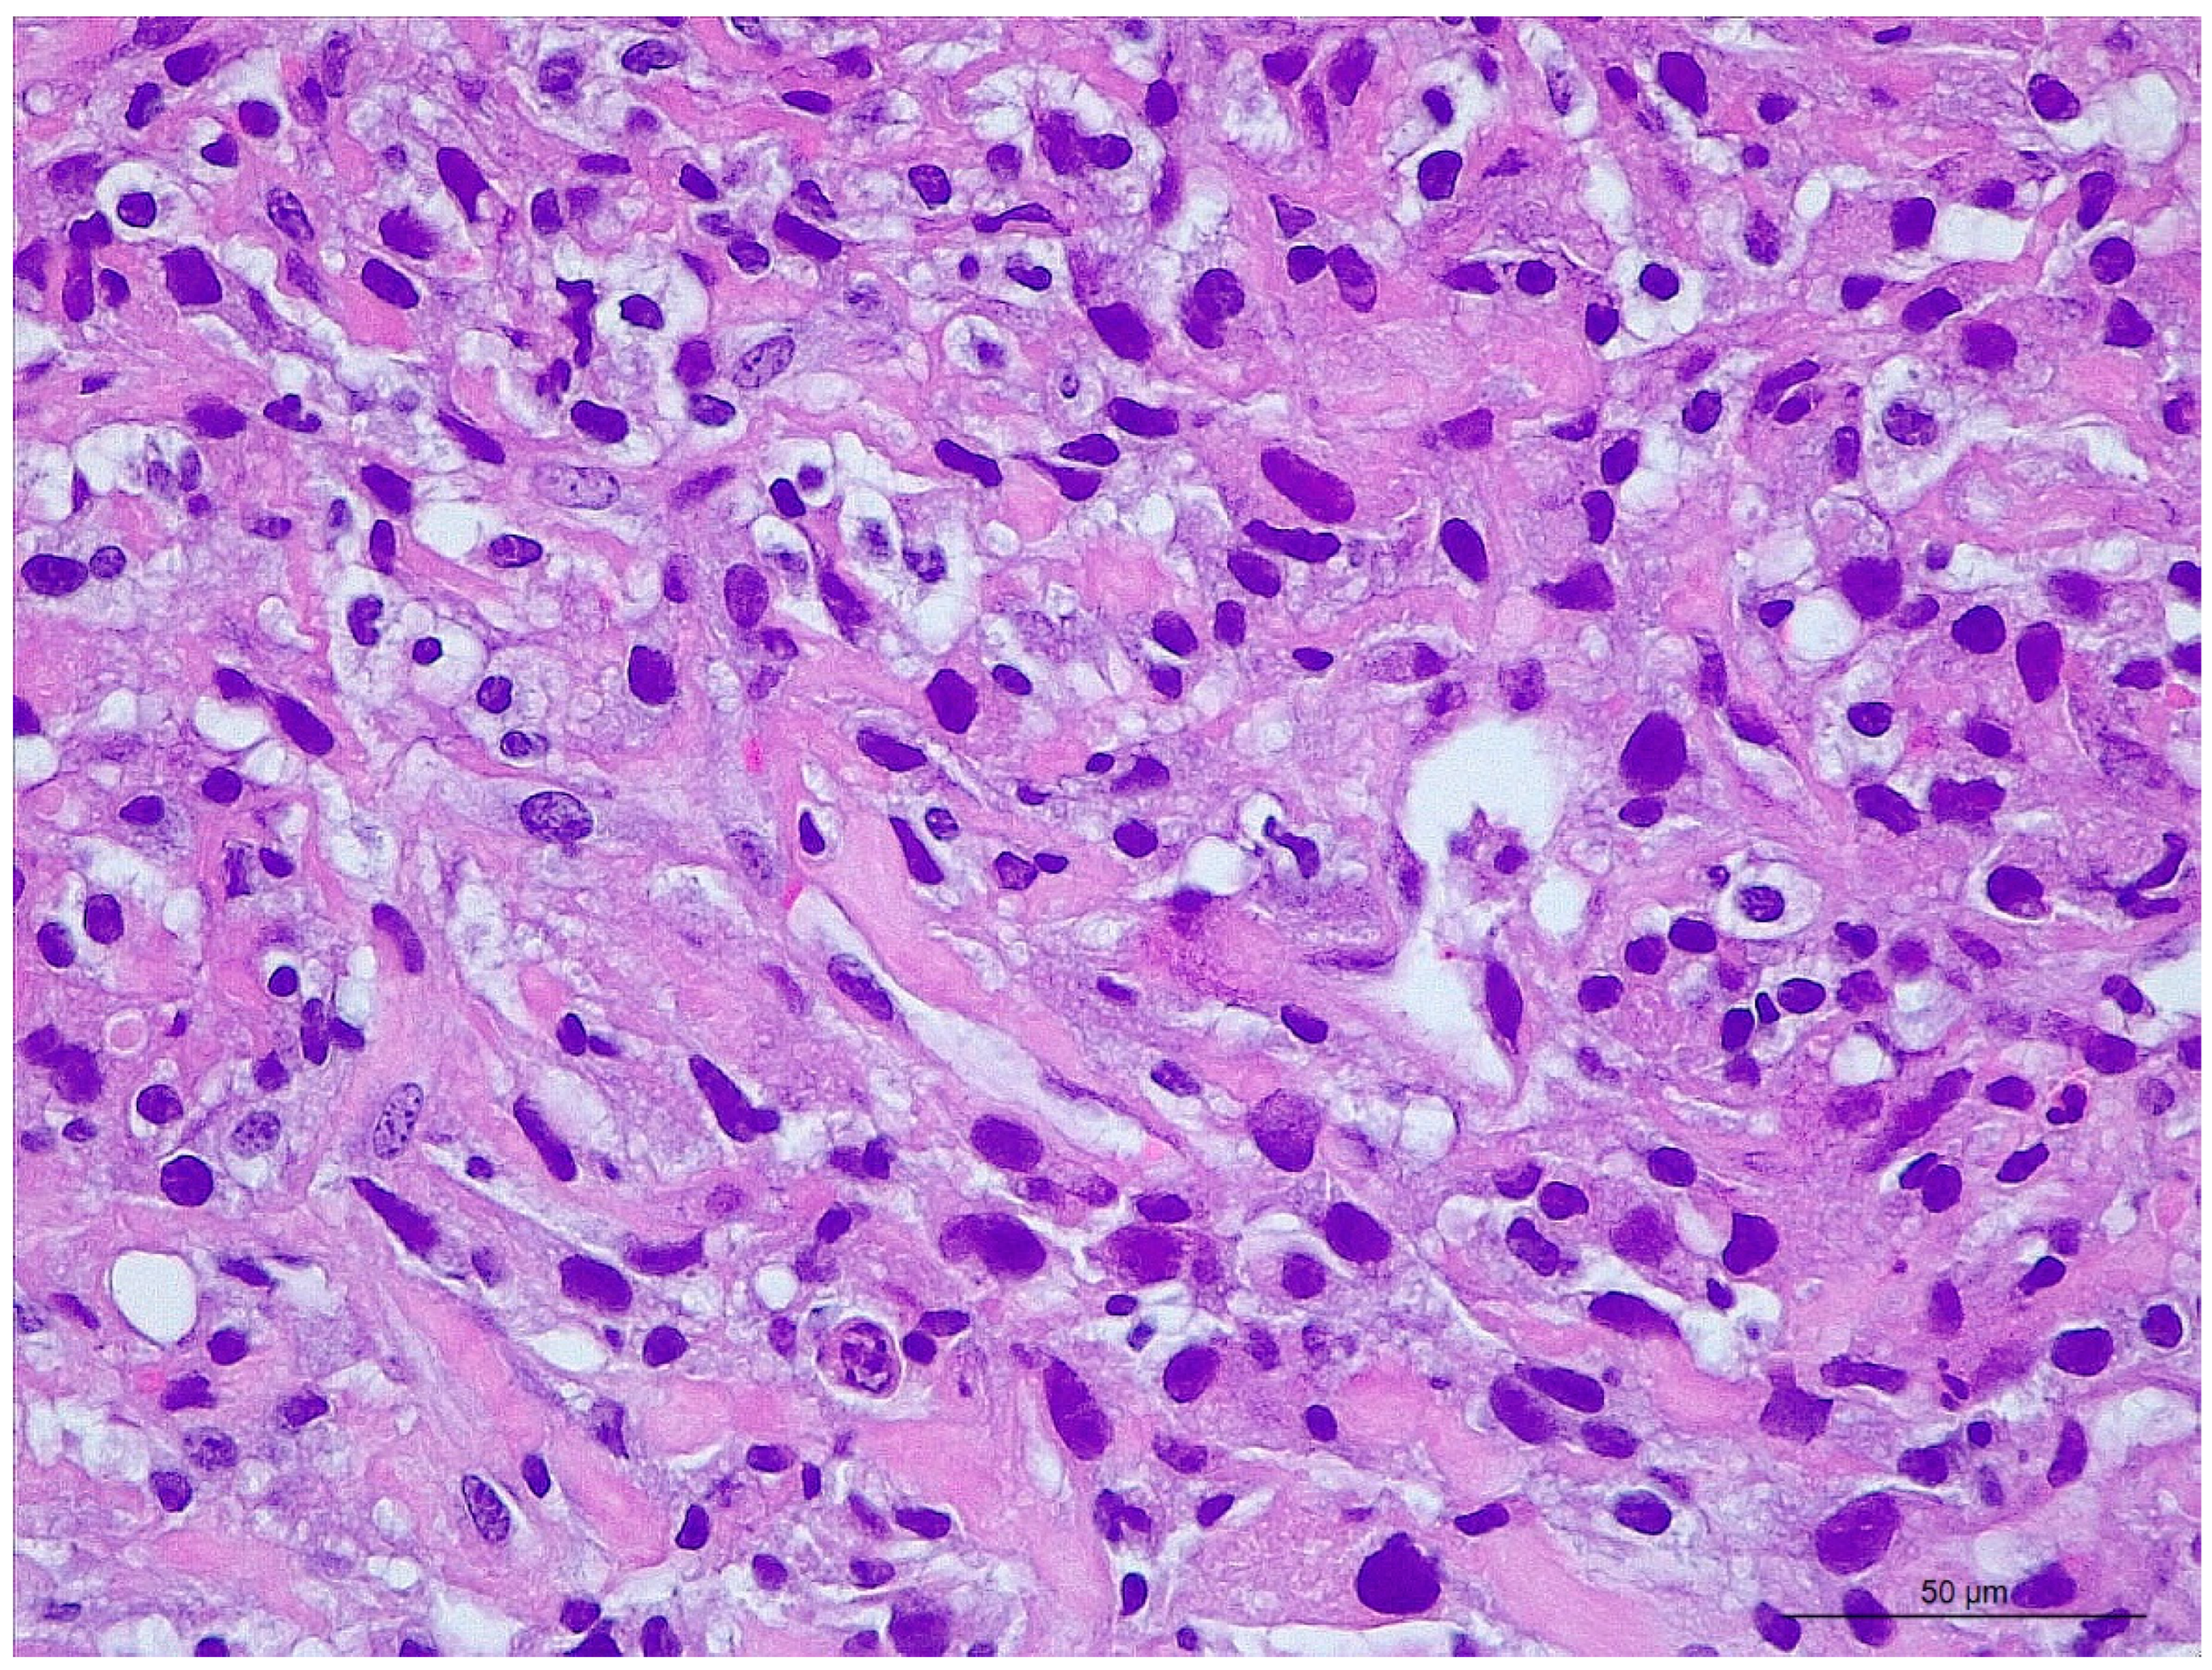

2.2. Final Diagnosis